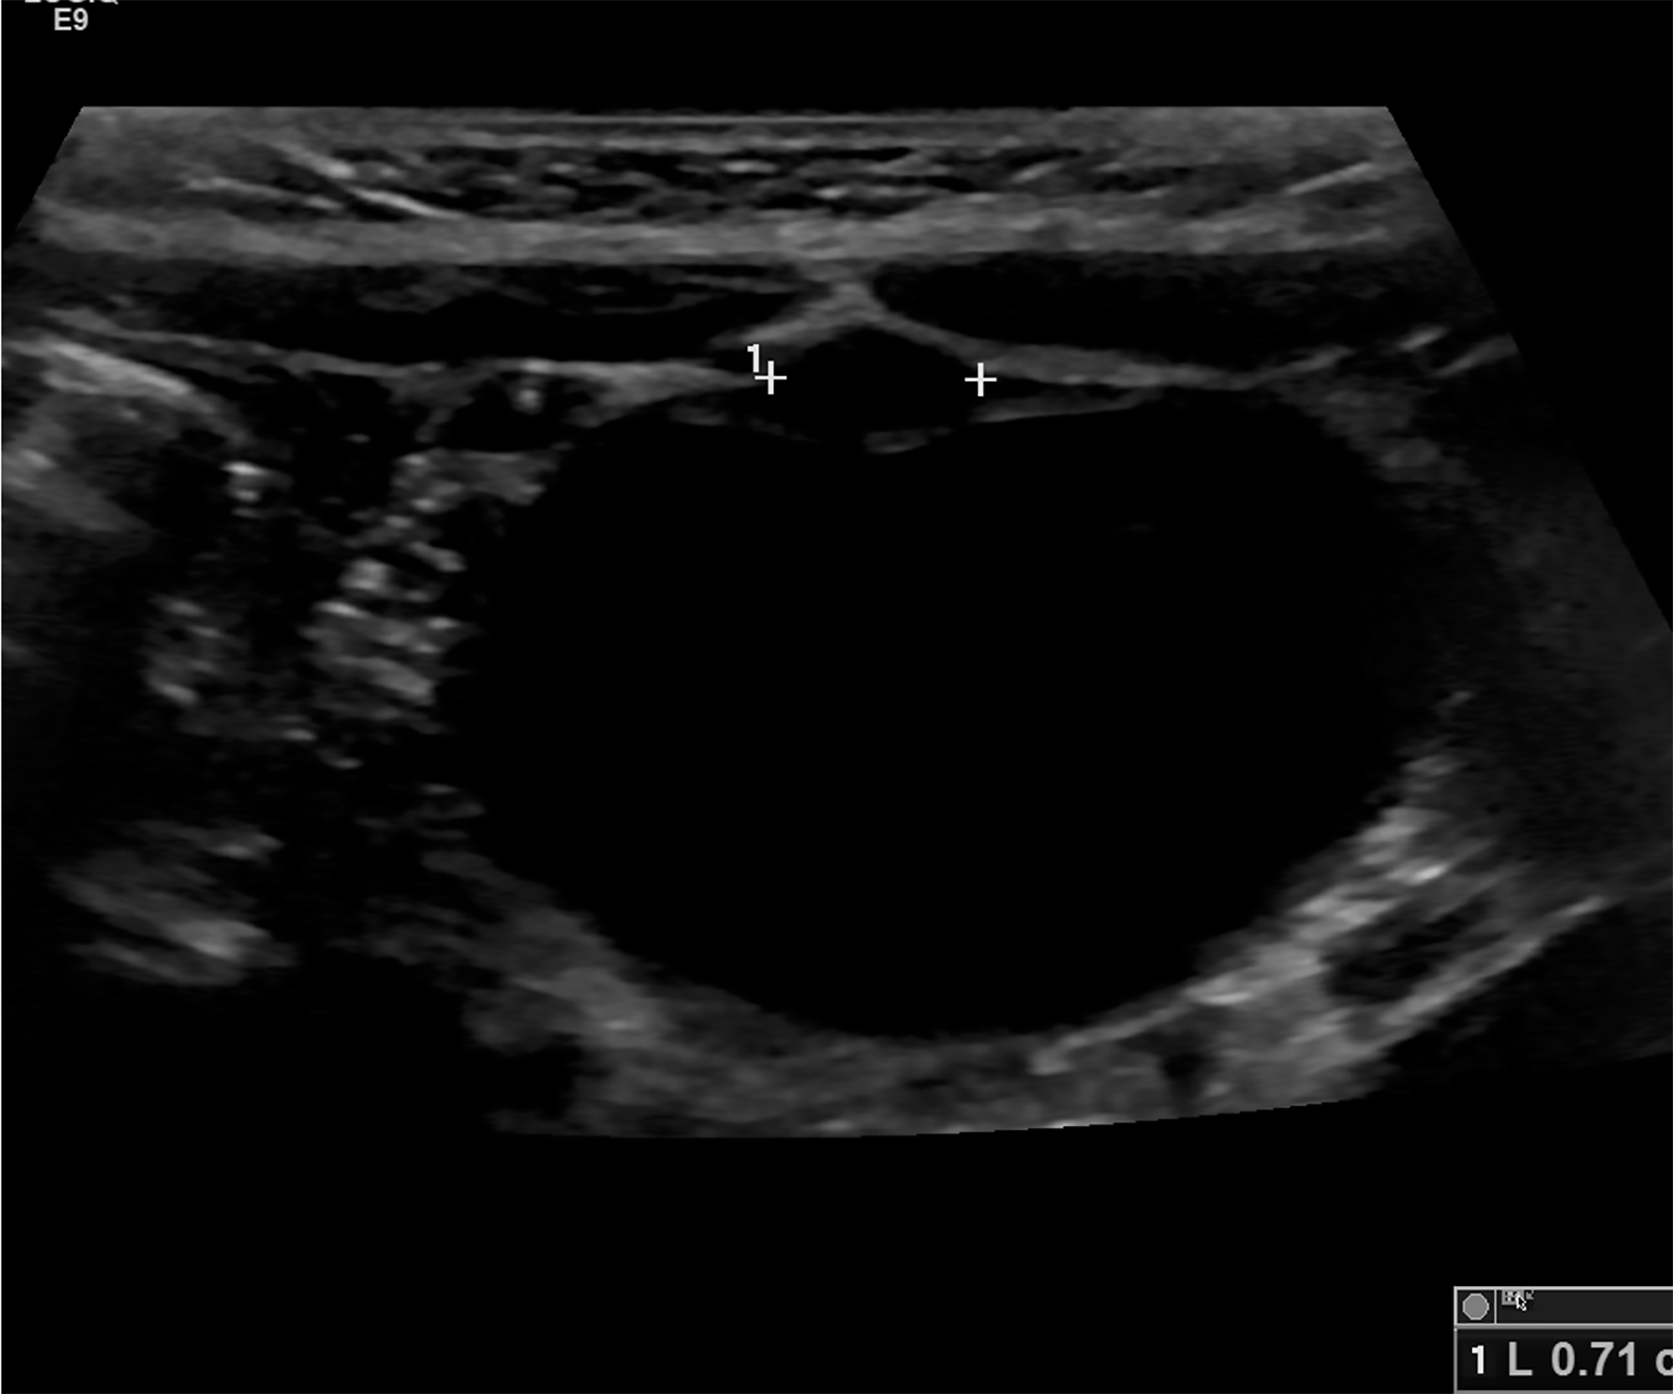

Figure 1 Shows an abdominal ultrasound that clearly identifies a hyperechoic focus anterior to the bladder as denoted by the number 1 on the figure.

This focus represents a urachal remnant and it extends between the two cross markers found in the image.